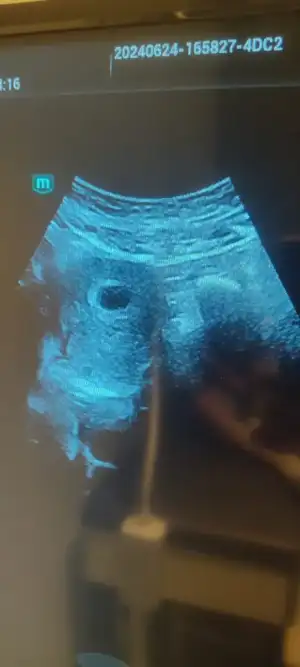

Aynıyız canım bende 5+4 üm bugün gördük keseyiKızlar merhaba Nasipse bende subat Ayı Annesi olacağım 5+4 deyim bugün kontrol için gittim kese gözüktü ama doktor yolk kesesi ile ilgili birsey söylemedi şimdide bos gebelikte ilgili şeyler okuyunca biraz endişe ettim sizce varmı yolk kesesi anlayan varsa çok sevinirim.